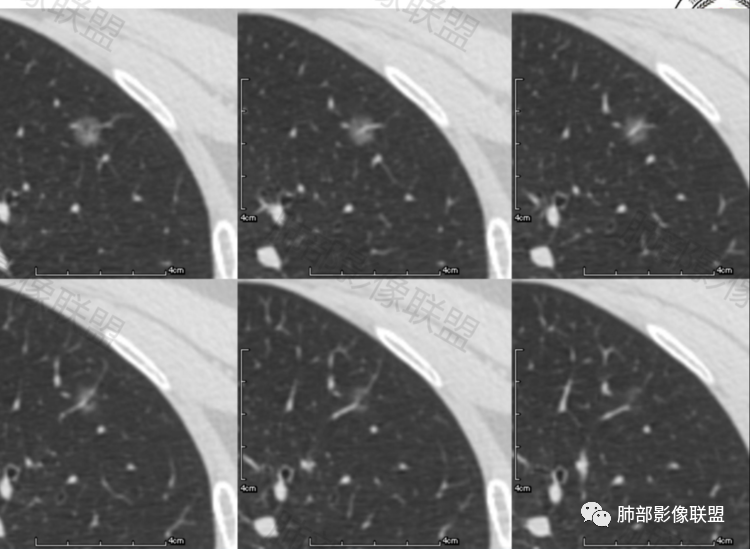

晨读,病例一:左肺磨玻璃结节,边缘清楚,内部有血管穿行自然,有低密度空泡?支气管?10个月后复查,结节增大0.2CM,不排除误差,考虑良性结节或炎性结节,继续短期随访。

病例一中年男性,左肺上叶纯磨玻璃结节,边界稍清,内部血管增粗,考虑炎性结节或AIS,建议抗炎治疗后三个月随访。

晨读:1 AIS 2AIS或者MIA偏后者 两者均可尝试抗炎,即便没吸收,6个月追踪

第一例纯磨玻璃结节,边界清,其内可见空泡,血管被拉直增粗,考虑MIA。病例二混合磨玻璃结节,边界清,血管贴边,考虑炎性病变,抗炎后复查,排除MIA。

2例磨玻璃结节,复查无吸收,增大约2mm,说明增大不明显,病例2月牙铲,病例1首先考虑AIS,继续追观复查;病例2考虑MIA

病例1,中年男性患者,左肺上叶尖端磨玻璃结节,边界清晰,内部见血管及空泡(也可能是支气管),10个月复查有轻微增大,考虑原位或微浸润,短期内随访,也可手术

病例一:中年男性,左上肺纯磨玻璃结节,边界清,无明显分叶,病灶内见血管穿行,血管隐约稍移位,内部隐约见小空泡,10个月复查 ,GGO持续存在稍稍增大,考虑AIS可能性大,建议继续随访(3个月)。